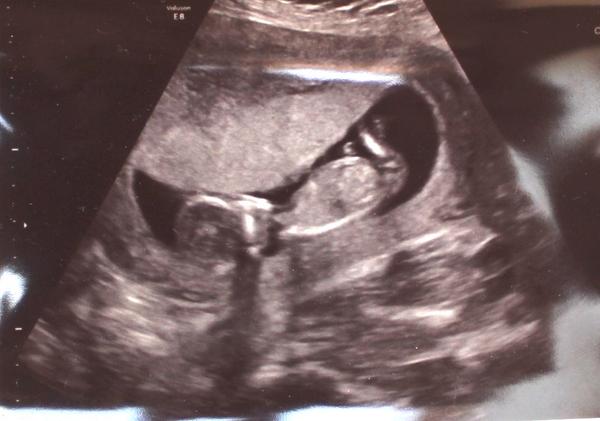

Je to holčička nebo chlapeček? Foto ultrazvuku

já jsme asi lehce mimo..ale část, kde je pohlaví vám na fotkách chybí,ne?:o) vidím obličejík a bříško..:o))

Ano,správně ☺je tady spousta fotek kde je jen hlavička a kousek bříška,tak jsem taky podobné přidala 😉 bohužel nám paní doktorka neudělala fotku nožiček...

Na UZ ve 14 tt nam rekli na 100% kluk a ted ve 22 tt, ze si neni jisty😳samozrejme je nam uplne jedno co to bude😍 ja za sebe tam vidim kavove zrno😊

@relax84 podle mě je to holčička ;) mně ji potvrdili teda až ve 20tt, protože měla pořád nožky křížem, ale vypadá to takto

No já vidím opravdu jasnou holčičku 🙂 tady snad nekdo o zom pochybuje,mam 3syny a obrázky jsem měla jiné relax85,nvo jineho by bylo kdyby nebyly nozicky takhle od sebe,kdyby to byl klučík,tak by výrazně čouhalo něco dopředu , ;) 🙂